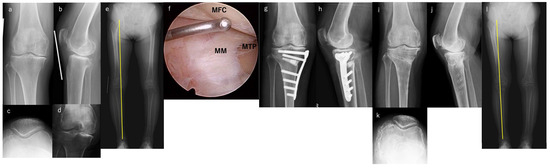

Experience of High Tibial Osteotomy for Patients with Rheumatoid Arthritis Treated with Recent Medication: A Case Series

by Yasuhiro Takahara, Hirotaka Nakashima, Keiichiro Nishida, Yoichiro Uchida, Hisayoshi Kato, Satoru Itani and Yuichi Iwasaki

Background: High tibial osteotomy (HTO) was generally not indicated in patients with rheumatoid arthritis (RA) because synovial inflammation may exacerbate joint damage postoperatively. Recently, joint destruction in RA has dramatically changed with the introduction of methotrexate (MTX) and biological disease-modifying antirheumatic drugs (bDMARDs). This study aimed to investigate the clinical outcomes of HTO for patients with RA treated with recent medication. Methods: In this study, patients with RA who underwent HTO between 2016 and 2020 were retrospectively reviewed. Patients whose follow-up period was <2 years and those whose onset of RA occurred after HTO were excluded. Clinical outcomes were investigated using the Japanese orthopedic Association (JOA) and visual analog scale (VAS) scores. Results: Seven patients (two males and five females, mean age 72.0 ± 6.2 years, mean body mass index 24.0 ± 2.9 kg/m2) were included in this study. The mean follow-up period was 62.1 ± 21.4 months. Open-wedge and hybrid closed-wedge HTO were performed in two and five cases, respectively. MTX was used for all cases. The bDMARDs were used in six cases (golimumab and tocilizumab in four and two cases, respectively). JOA scores significantly improved from 63.6 ± 10.7 preoperatively to 90.7 ± 5.3 postoperatively (p = 0.0167 Wilcoxon rank test). VAS scores significantly decreased from 48.6 ± 12.2 preoperatively to 11.4 ± 6.9 postoperatively (p = 0.017 Wilcoxon rank test). None of the patients underwent total knee arthroplasty. Conclusions: This study showed seven RA patients who underwent HTO treated with recent medication. The prognosis of RA, including joint destruction, has dramatically improved with induction of MTX and bDMARDs. HTO may be one of effective joint preservation surgeries even for patients with RA. To achieve the favorable outcomes, surgeons should pay attention to timing and indication of surgery. Full article

Show Figures

Figure 1